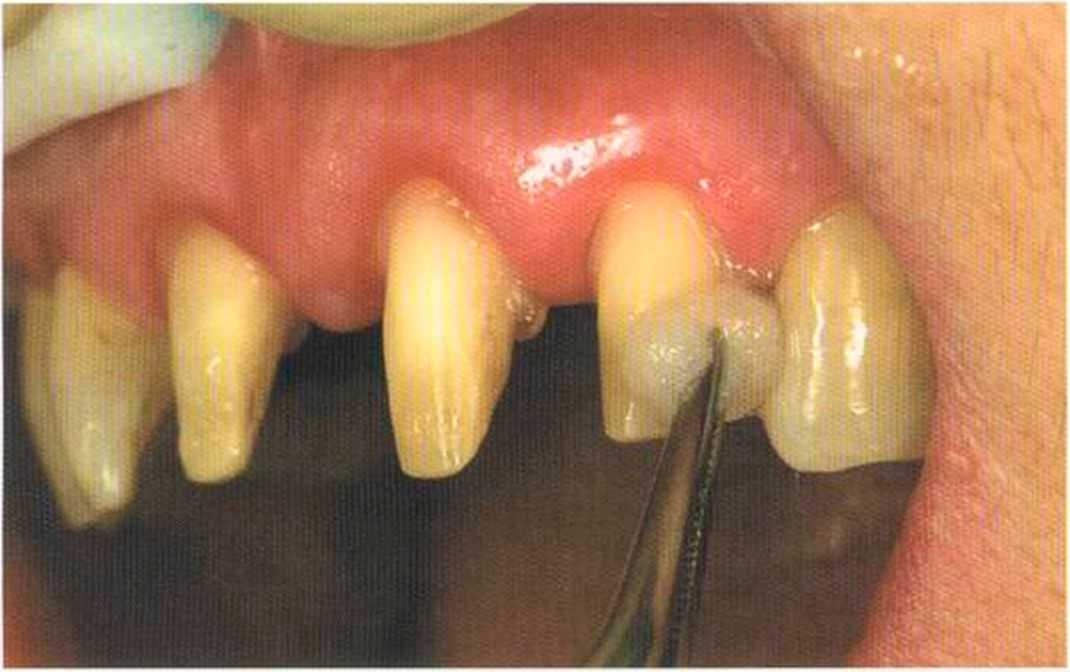

Этот пациент — португалец. Он всю жизнь имел такое положение зубов. Небнорасположенный боковой резец теперь необходимо удалить, а затем воссоздать как эстетику, так и функцию в области фронтальной группы зубов. Планируется изготовить коронки In-Ceram в области 11 и 21 и соединить их вместе из-за увеличивающейся подвижности зубов.

Препарирование, проводимое доктором Риссе, оценивается как очень сложное. Режущие края центральных резцов сильно дивергируют, что создает неудобство при формировании хорошего уступа.

Фото сверху и слева: отличный результат препарирования зубов с уже уложенными нитями для снятия оттиска.